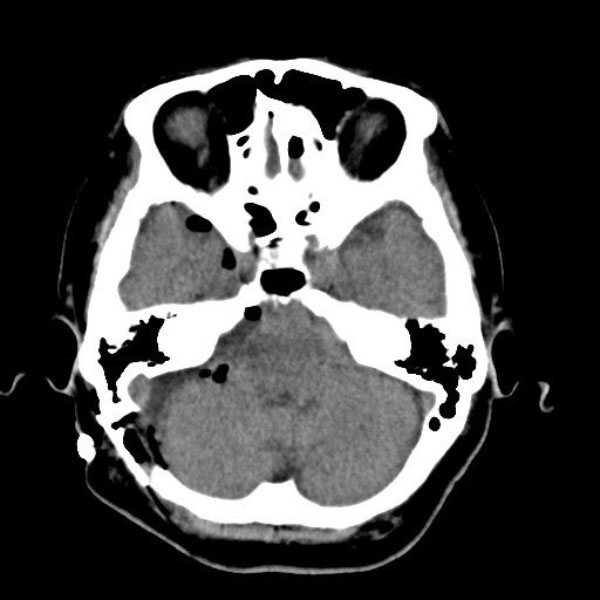

手術後

(CT)